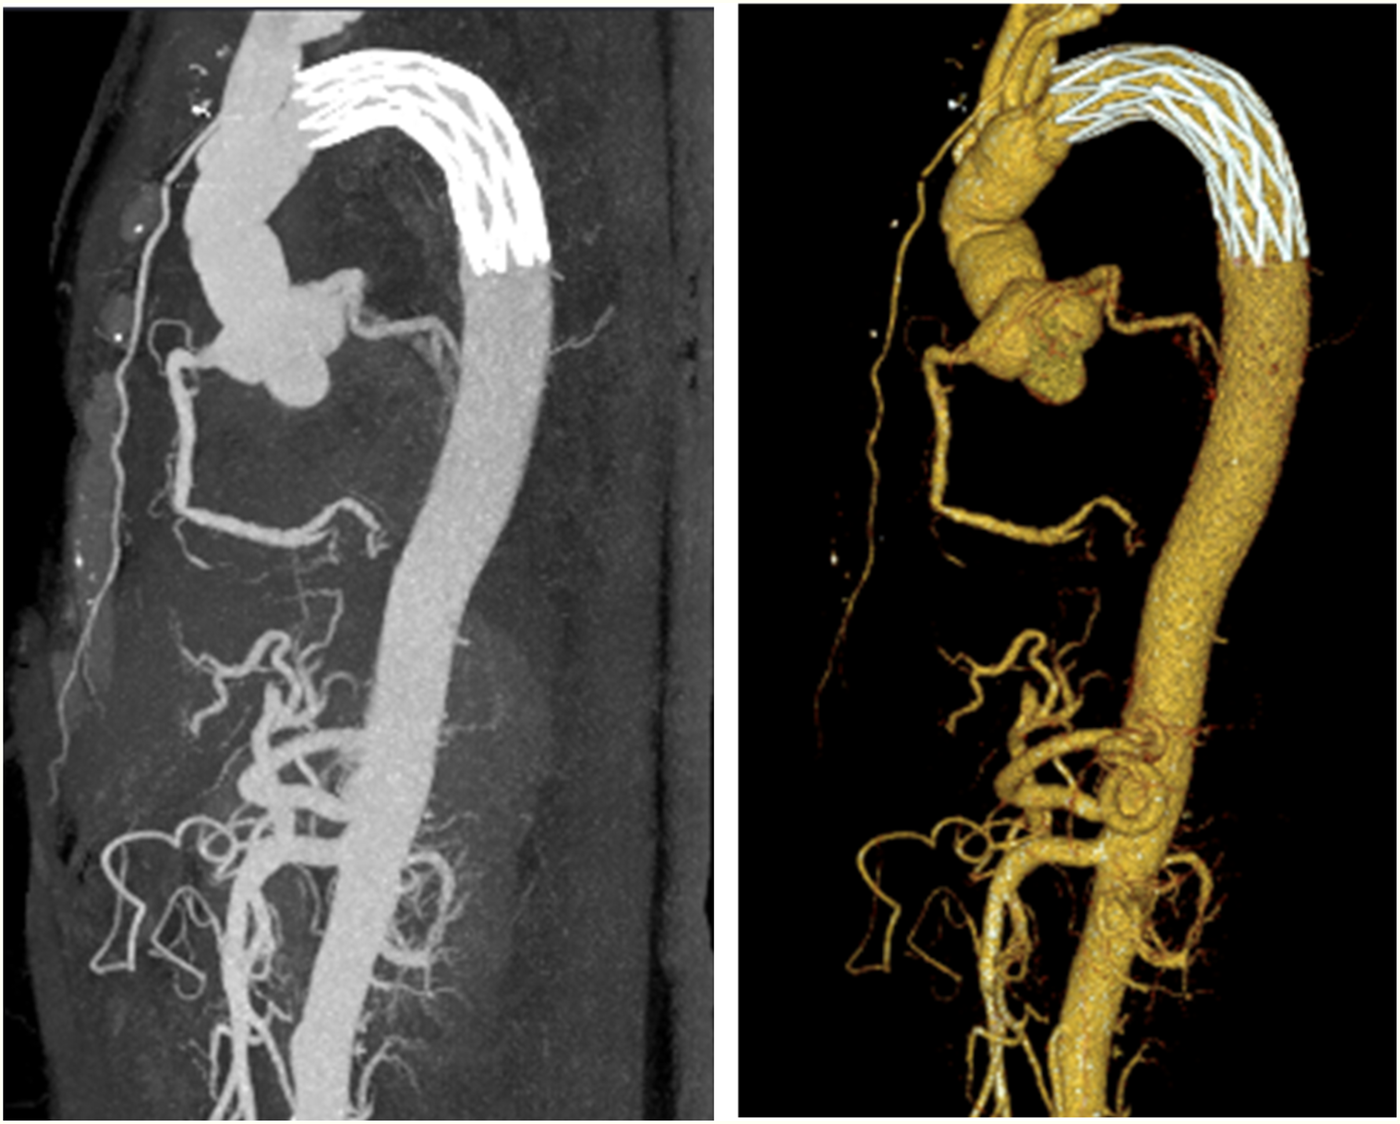

Figure 5

Computed tomography conducted after aortic arch artificial vessel replacement.

Partial resection of the ascending aorta with artificial vascular graft replacement (Figure 5).

Total aortic arch replacement using a stent-assisted elephant trunk procedure (Sun's procedure).

Intraoperative pericardiotomy suggested approximately 500 mL of hemorrhagic effusion and clots. The patient was transferred to the general cardiac ward on 13 January 2025 and was discharged on 26 January 2025, after a successful recovery. Follow-up continued through 1 June 2025. The Department of Cardiothoracic Surgery conducted follow-up examinations on 27 February, 27 March, 24 April, and 29 May. Cardiac ultrasound and chest x-ray were performed at each visit, and no notable abnormalities were found.